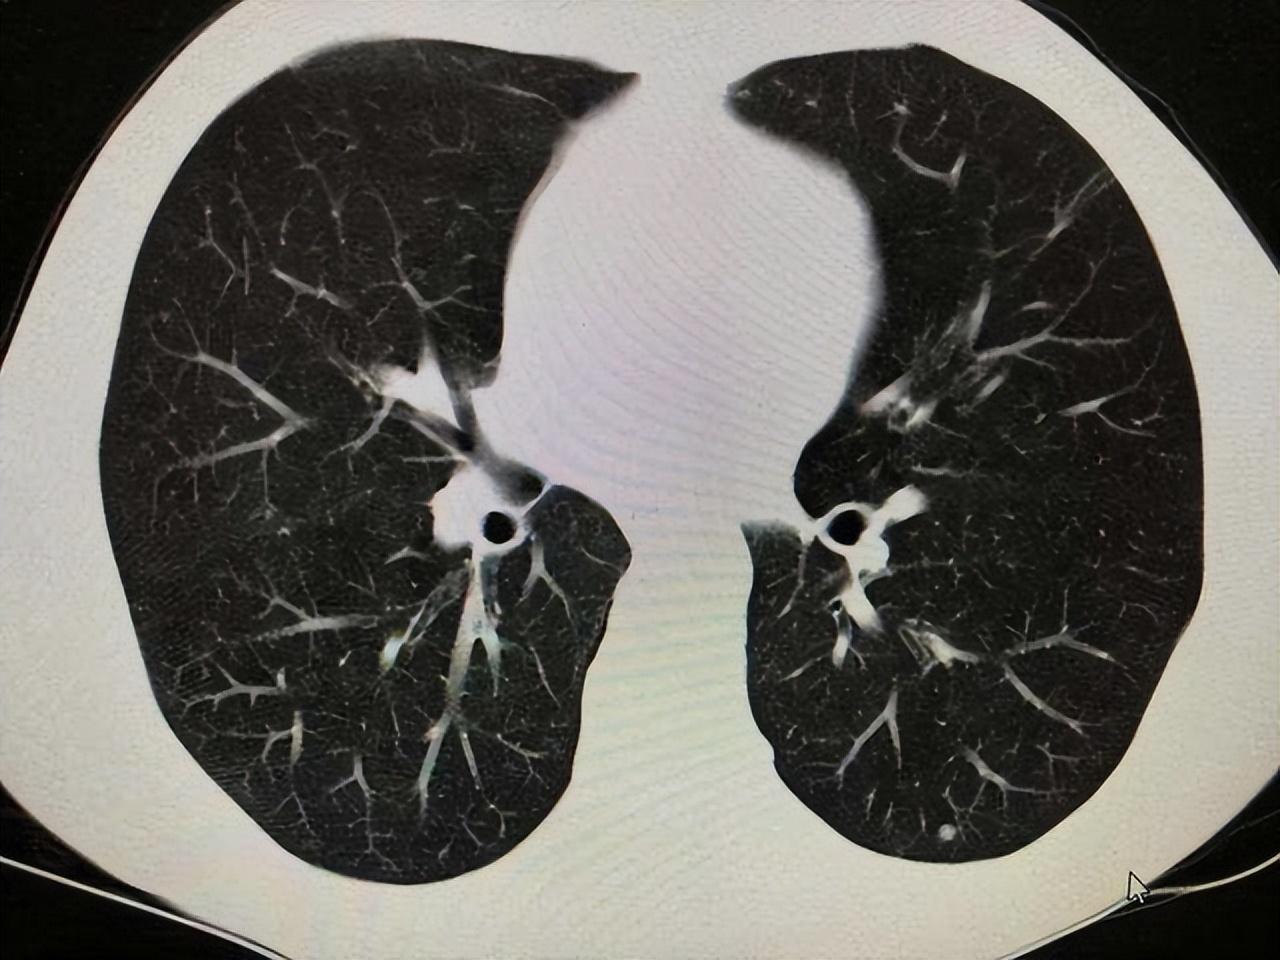

關(guān)于打科興后出現(xiàn)肺結(jié)節(jié)的探討,科興疫苗接種與肺結(jié)節(jié)關(guān)系探討

摘要:近期有關(guān)接種科興疫苗后出現(xiàn)肺結(jié)節(jié)的問題引發(fā)關(guān)注。研究表明,科興疫苗安全有效,未發(fā)現(xiàn)與肺結(jié)節(jié)有直接關(guān)聯(lián)。一些人因個(gè)體差異可能在接種疫苗后出現(xiàn)肺結(jié)節(jié),但這種情況極為罕見。專家建議,如有疑慮,可定期進(jìn)行肺部檢查,關(guān)注...